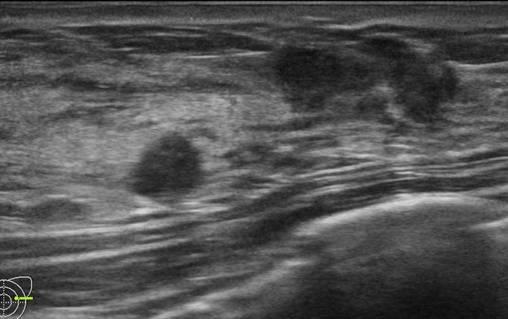

Ung thư vú

» Thông tin: Nữ giới – 25 tuổi.

» Lâm sàng: Khối tuyến vú.